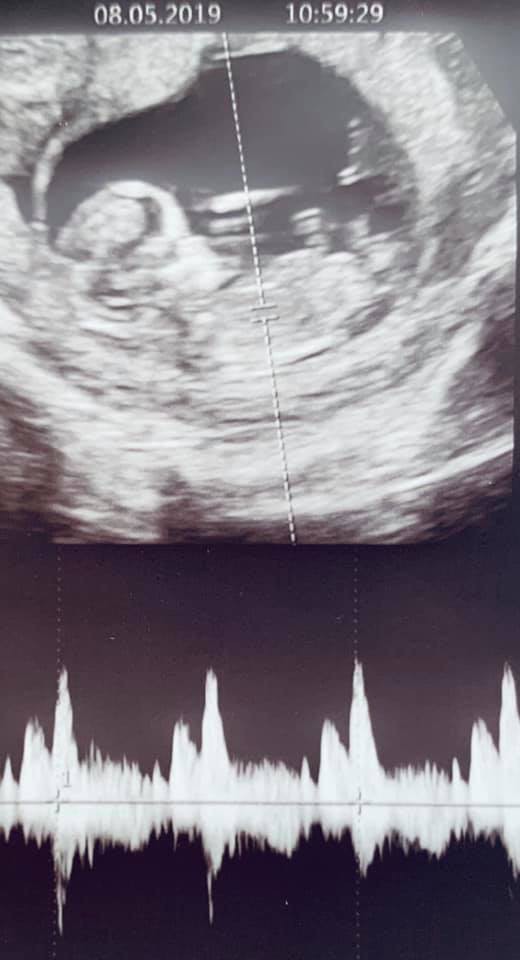

Cho tới mới đây, ông xã của Lan Khuê - doanh nhân John Tuấn Nguyễn đã chính thức xác nhận thông tin này trên trang cá nhân. Theo đó, ngoài đăng bức ảnh siêu âm thai nhi, John Tuấn Nguyễn đã chia sẻ bằng tiếng Anh: "My lil’ bugga baby. The feels you get when you hear your kid’s heart beating healthy and they wave their hand at you from inside the womb. Life just got really real". (Tạm dịch: Em bé của tôi. Cảm giác bạn có được khi nghe trái tim con bạn đập khoẻ mạnh và chúng vẫy tay với bạn từ trong bụng mẹ. Cuộc sống thật sự rất tuyệt vời".

Chia sẻ này của John Tuấn Nguyễn đã mau chóng nhận được rất nhiều lời chúc mừng từ bạn bè, khán giả. Dù đến hiện tại, vợ chồng Lan Khuê - John Tuấn Nguyễn vẫn chưa tiết lộ thêm về con đầu lòng hay quá trình mang thai nhưng thông tin này đã khiến người hâm mộ của cặp đôi vô cùng vui mừng.